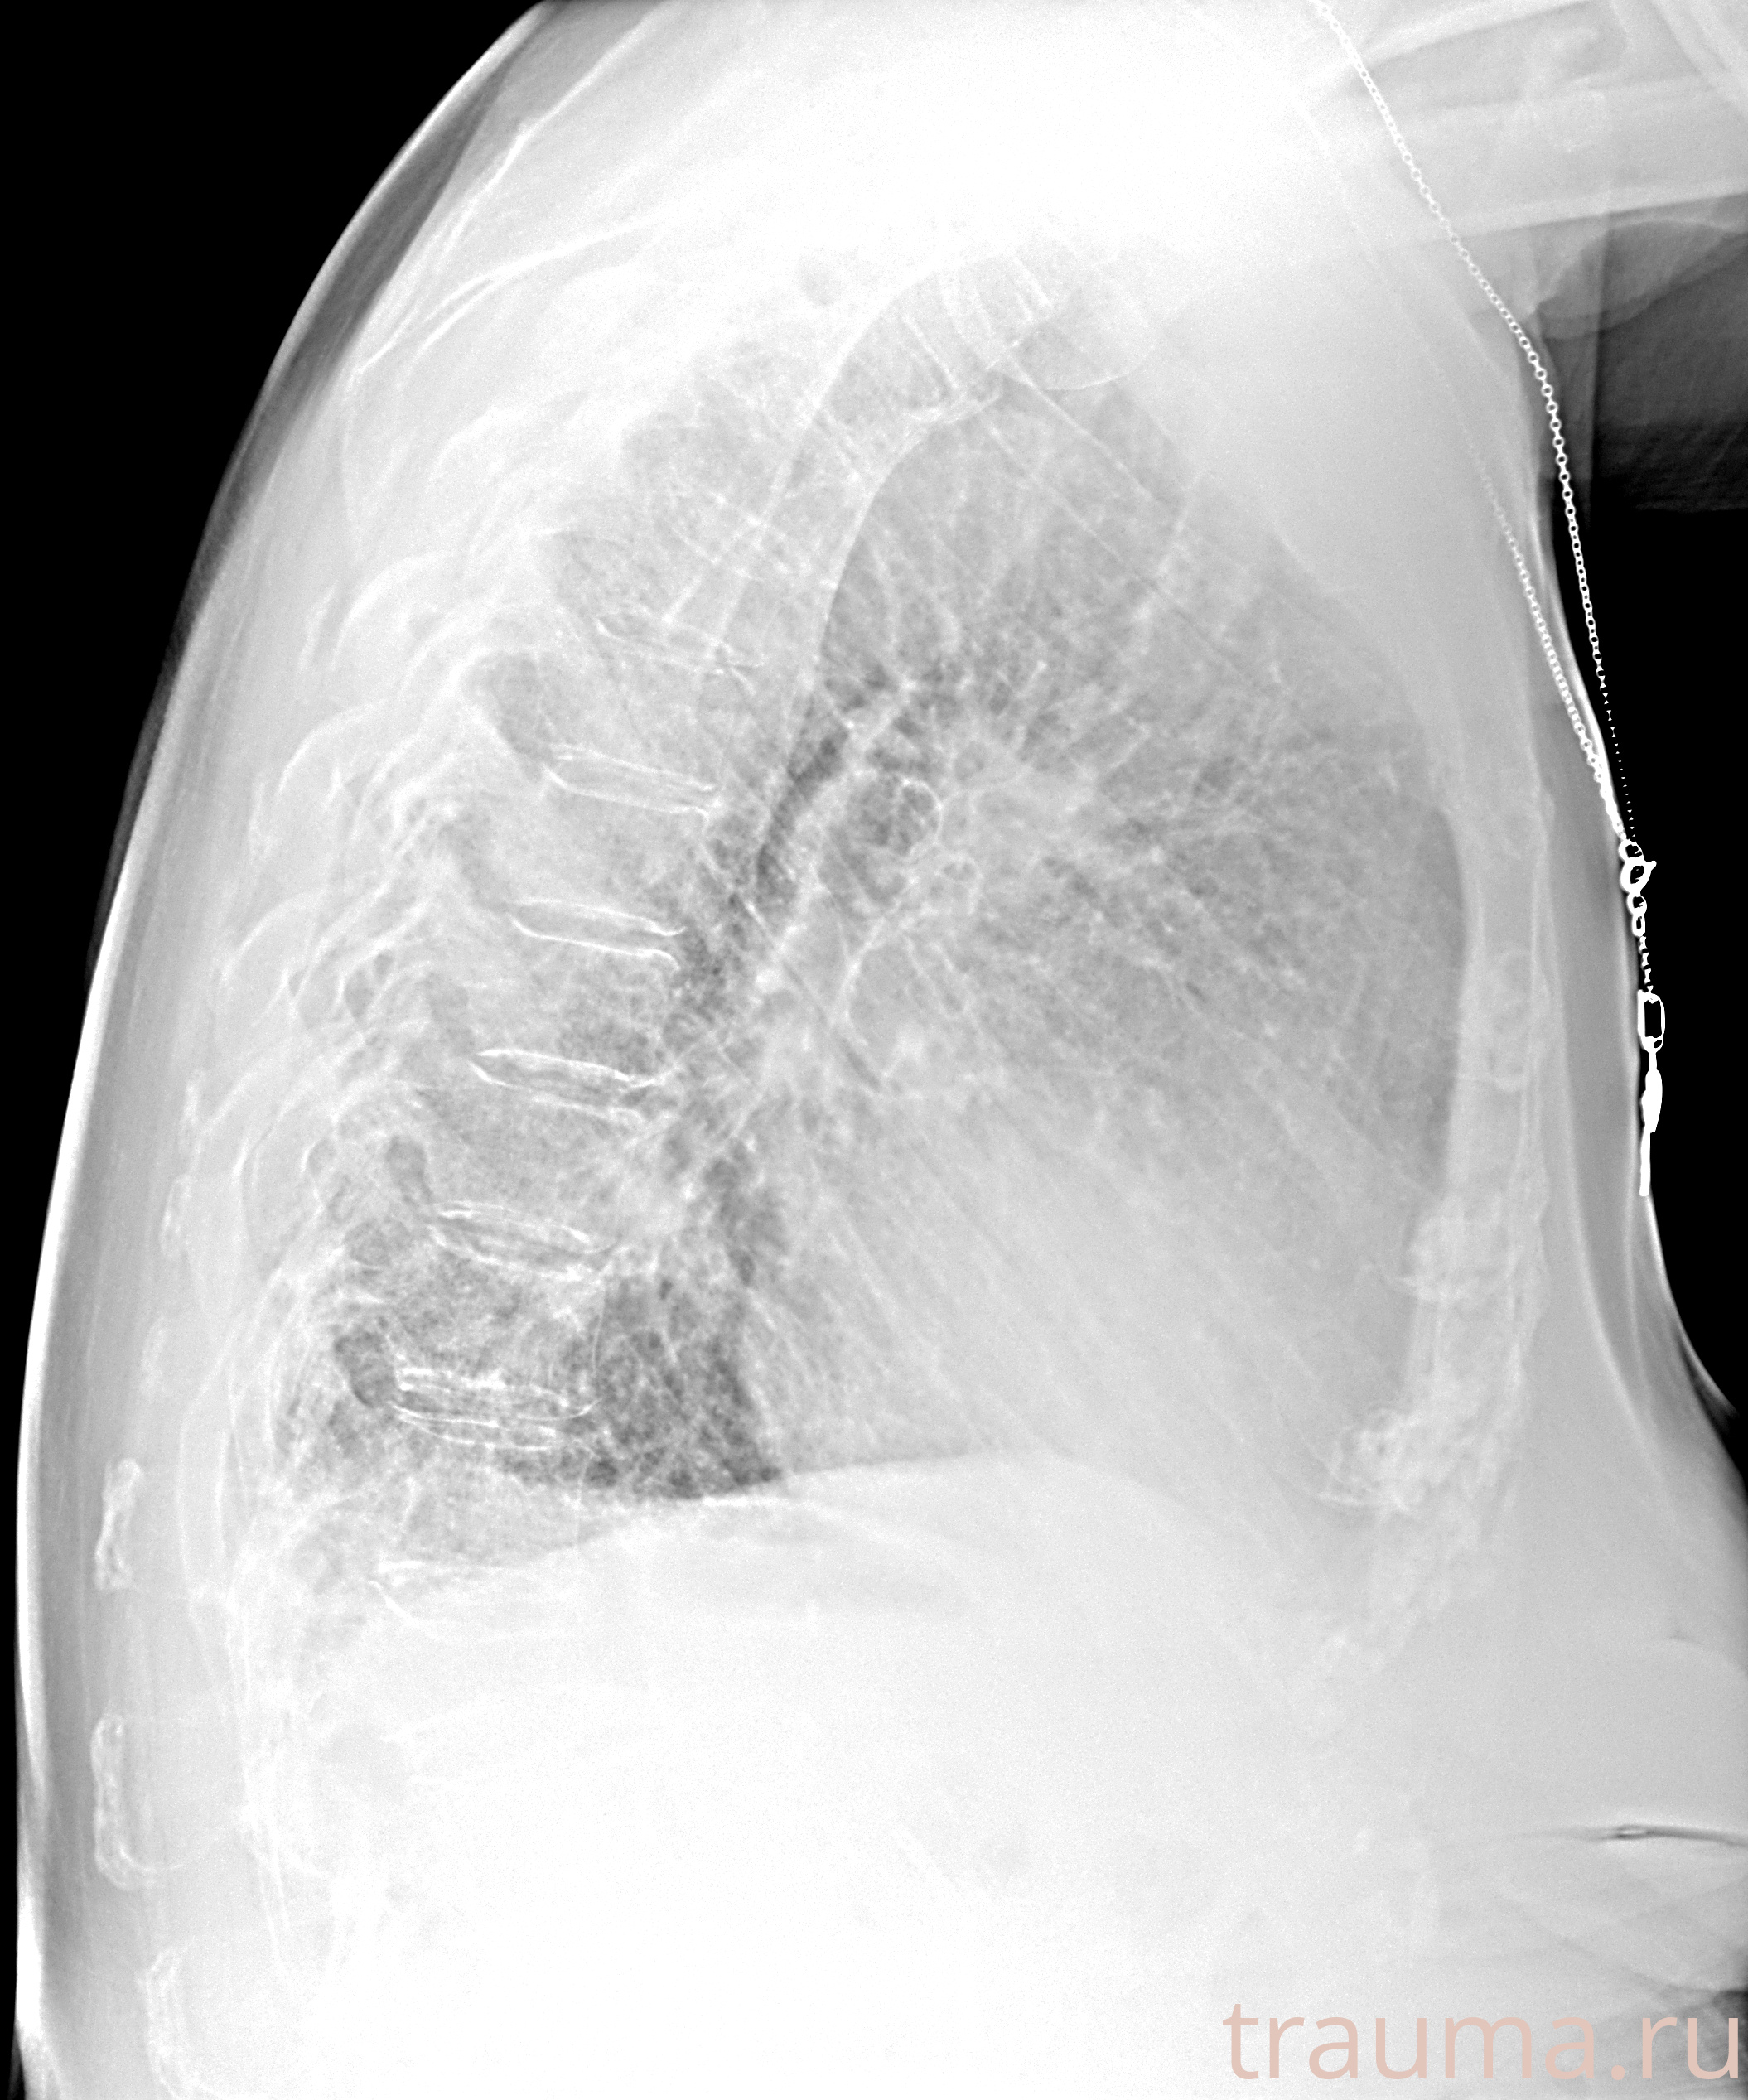

Рентгенограммы

Рентген на дому: по вашему адресу приезжает врач-рентгенолог, травматолог-ортопед с мобильным рентгеновским аппаратом, проводит диагностику травмы или заболевания, делает необходимые рентгенограммы, дает рекомендации по дальнейшему лечению. Получить качественные снимки в домашних условиях возможно благодаря уникальной методике, разработанной МосРентген Центром для института  Склифосовского